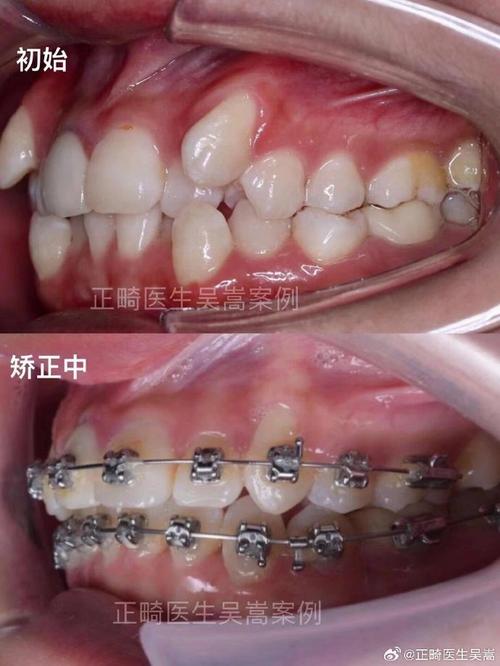

- 查看案例与资质:要求医生展示相似案例前后对比,确认机构是否具备《医疗机构执业许可证》,医生是否在卫健委官网可查。